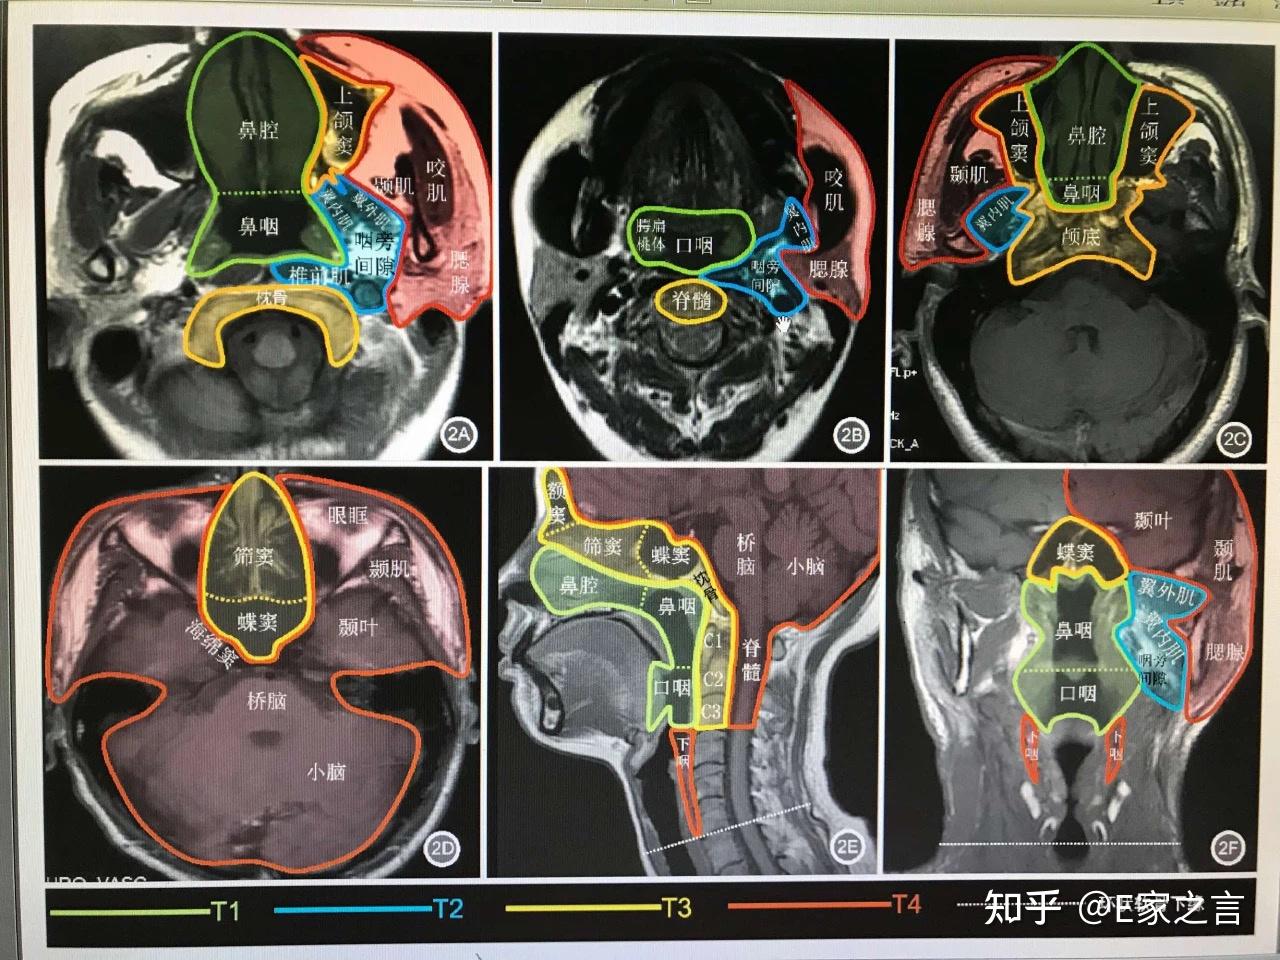

鼻咽癌的ct诊断与鉴别诊断整理